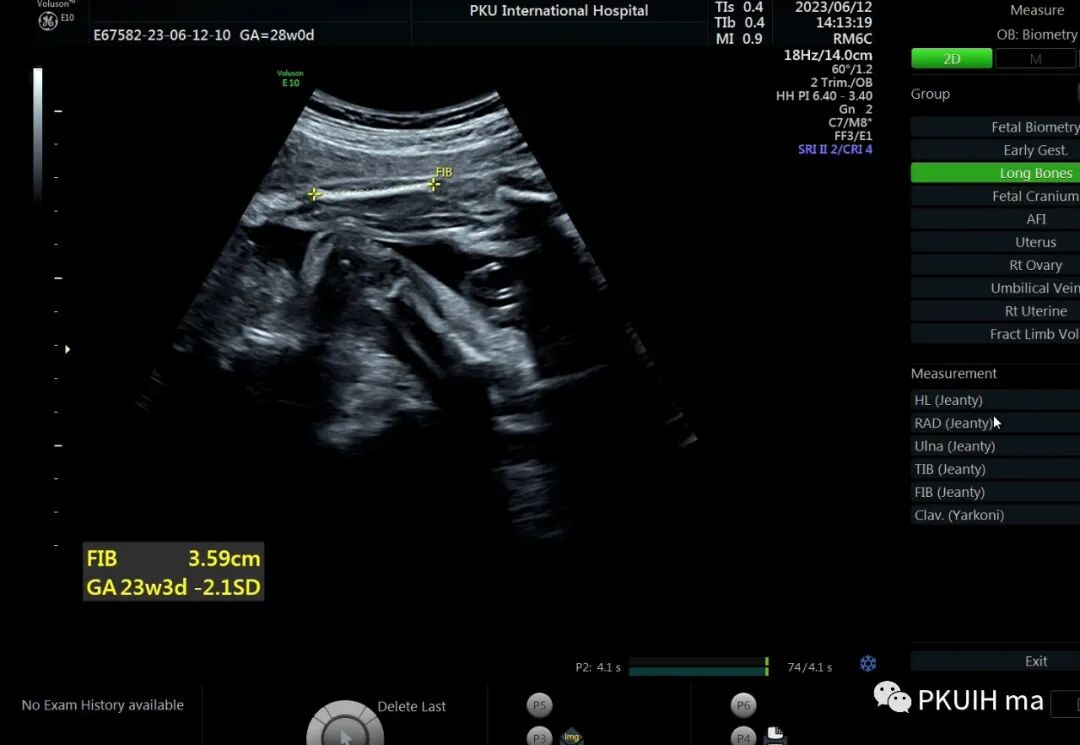

28周检查发现肢体越来越短

头围双顶径大于28周,骨骼回声强度未见明显异常